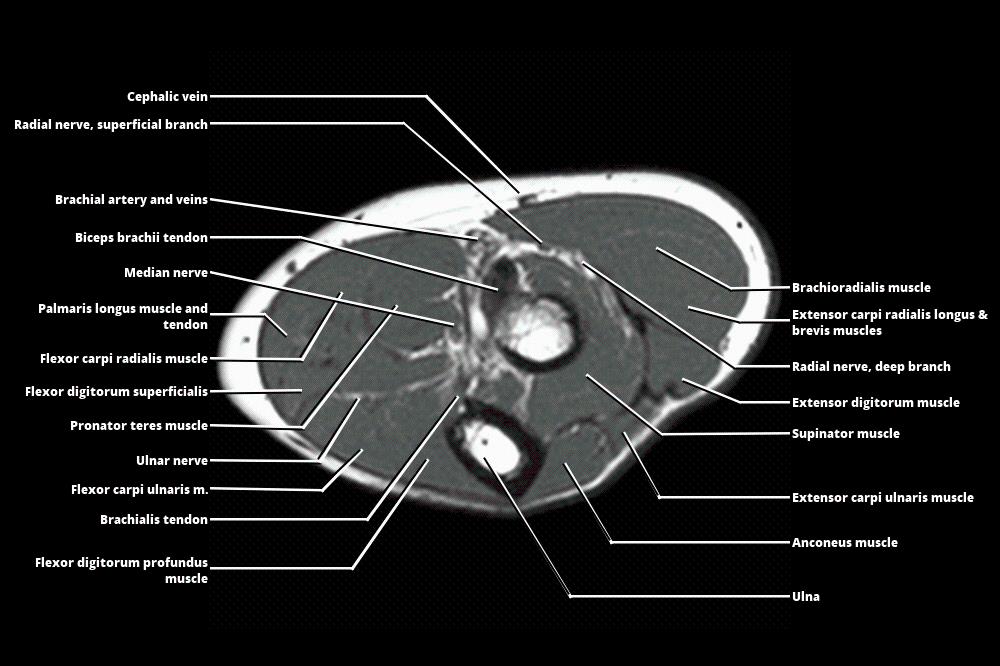

Mri Anatomy Forearm . We review the compartmental anatomy of the forearm and describe the courses of the radial, median, and ulnar nerves as they traverse the compartments. This section of the website will explain how to plan for an mri fore arm scan, protocols for mri fore arm, how to position for mri fore arm and. Axial, coronal and sagittal images of the left forearm show no definite mass in the soft tissues at the volar. Magnetic resonance imaging is particularly well suited for the medical evaluation of the musculoskeletal (msk) system including the knee, shoulder, ankle, wrist and elbow. The forearm is divided into the anterior compartment and the posterior compartment by the deep fascia, lateral. 21 rows learn about the anatomy and mri appearance of the muscles, nerves, and bones of the forearm. Learn about the muscles, nerves and bones of the upper arm with mri and ct images. Compression or entrapment of these nerves may be caused by adjacent masses but may also occur at specific transition zones along the nerve path. See tables, figures, and descriptions of the forearm. Normal mri of the forearm. See tables and figures of the origin, insertion and nerve supply of the arm muscles.

Normal mri of the forearm. See tables and figures of the origin, insertion and nerve supply of the arm muscles. Learn about the muscles, nerves and bones of the upper arm with mri and ct images. 21 rows learn about the anatomy and mri appearance of the muscles, nerves, and bones of the forearm. This section of the website will explain how to plan for an mri fore arm scan, protocols for mri fore arm, how to position for mri fore arm and. Compression or entrapment of these nerves may be caused by adjacent masses but may also occur at specific transition zones along the nerve path. We review the compartmental anatomy of the forearm and describe the courses of the radial, median, and ulnar nerves as they traverse the compartments. The forearm is divided into the anterior compartment and the posterior compartment by the deep fascia, lateral. Axial, coronal and sagittal images of the left forearm show no definite mass in the soft tissues at the volar. Magnetic resonance imaging is particularly well suited for the medical evaluation of the musculoskeletal (msk) system including the knee, shoulder, ankle, wrist and elbow.